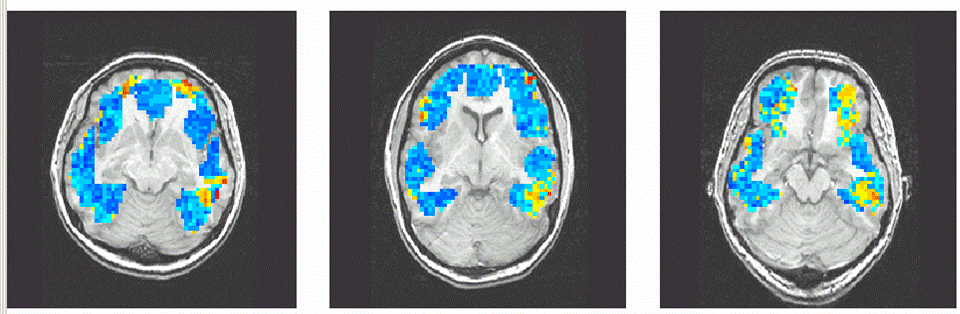

经过一些数据处理,实验员告诉我,他们已经分解出了刚才的过程,那些状态下我看的是建筑物,而哪些又是动物,通过我大脑的变化可以一目了然。

核磁共振仪的主磁场校正小磁球的旋转方向,激发磁场不断开关,将小磁球拉向一个方向,反复这个过程,小球就会不断的歪过来,倒过去,产生的电磁波就可以被接收到,从而处理成图像。不同组织中磁场强度不同,我们就可以在图像上区分大脑的灰质、白质、脑脊液等组织了。人脑活动时的血流变化也能被这种方式检测到,我们就通过血液的流动,判断哪些部分的脑组织正在工作。

过去十几年的研究,我们一直在给认知活动寻找地址,例如,读词时某脑区活动,看画时则是另一个脑区。这就好像是在墙上寻找斑点,我们只关心斑点所在的位置。现在,一种称为多体素模式分析的范式改变了思路,我们不再关心某个斑点的位置,而是寻找大量斑点组成的模式。通过计算机模式识别,就可以判断大脑的状态,甚至读出大脑的活动。